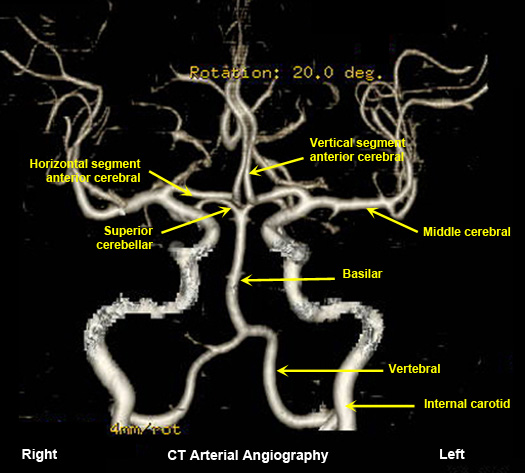

Normal CT arterial angiography

Contrast administered intravenously. |